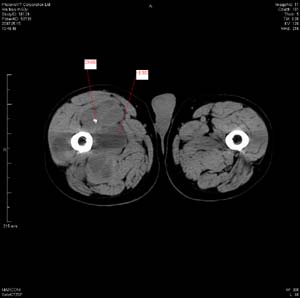

男 63岁 右大腿无痛性肿块11年,x片右大腿软组织肿块影,余无明显异常.ct值-13__239hu

右大腿股内侧股与收肌间隙间多发囊实性占位,界清.内示斑点状钙化.局部骨质无异常.肌肉推压移位表现.

考虑肌间隙病变.可有1,神经来源肿瘤.2,血管来源病变.3,淋巴来源肿瘤.4,脂肪来源肿瘤.5,滑膜来源肿瘤.结合病史只能考虑良性占位.建议增强或mri进一步分析.

同意,病史较长,病变周围分界清晰,考虑良性病变。病灶内有多发斑点状钙化,沿肌间隙生长,血管瘤或淋巴管瘤首先考虑。